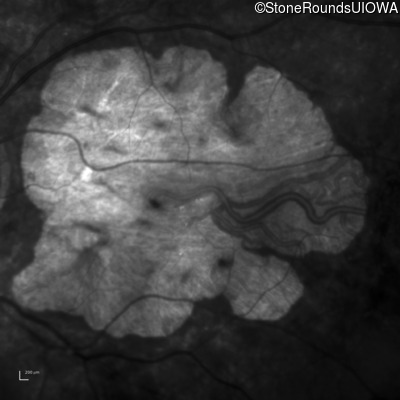

Age at visit: 43 years

OD OS